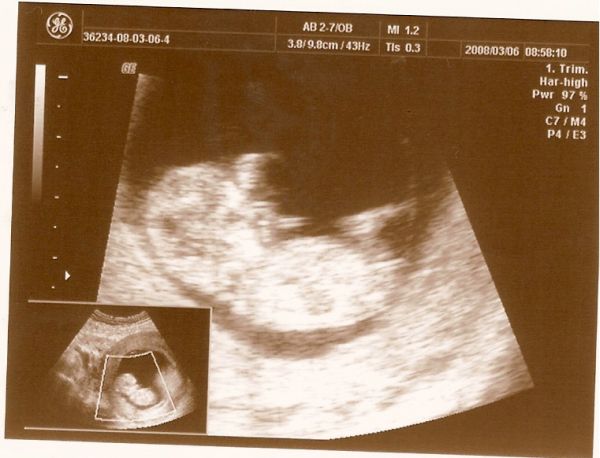

CRL: 6cm, tarkóredő: 1.2mm

Mi is tegnap voltunk.Képet is teszek majd, de most csak gyorsan.

CRL:5,34 cm

tarkóredő:1mm, ami nagyon tetszik combcsont: 5mm! milyen picurka, máris imádom :) megvannak az orrcsontok is.

Továbbra is nagyon elégedett vagyok a dokival, mért és mondott is mindent kérés nélkül.Sőt még azt is megmondta 95%-os biztosággal, ha akarjuk persze,hogy kisfiú vagy kislány csücsül odabennt.A páromra biztam a döntést, ő szerette volna tudni /én is :lol: /, szóval kislány!